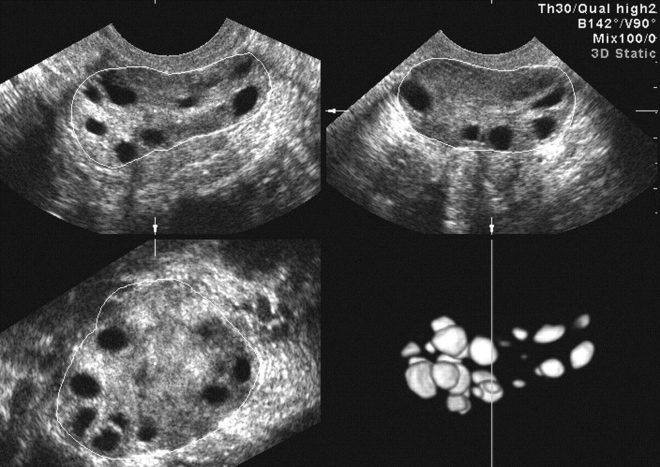

Увеличение размера яичника